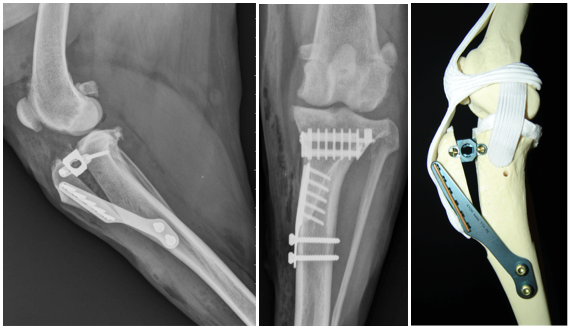

TTA                                         TPLO                                     CCWO

Specialisatie Patella luxatie ( losse knie)  kruisband herstel bij hond en correctieve osteotomies , kunstgroeve, kunstknie bij hond en kat .

sept 2023  securos Londen  TPLO en CCWO

April 2019  KYON Corrective osteoyomy of the hind limb and patella groove  Zwitserland